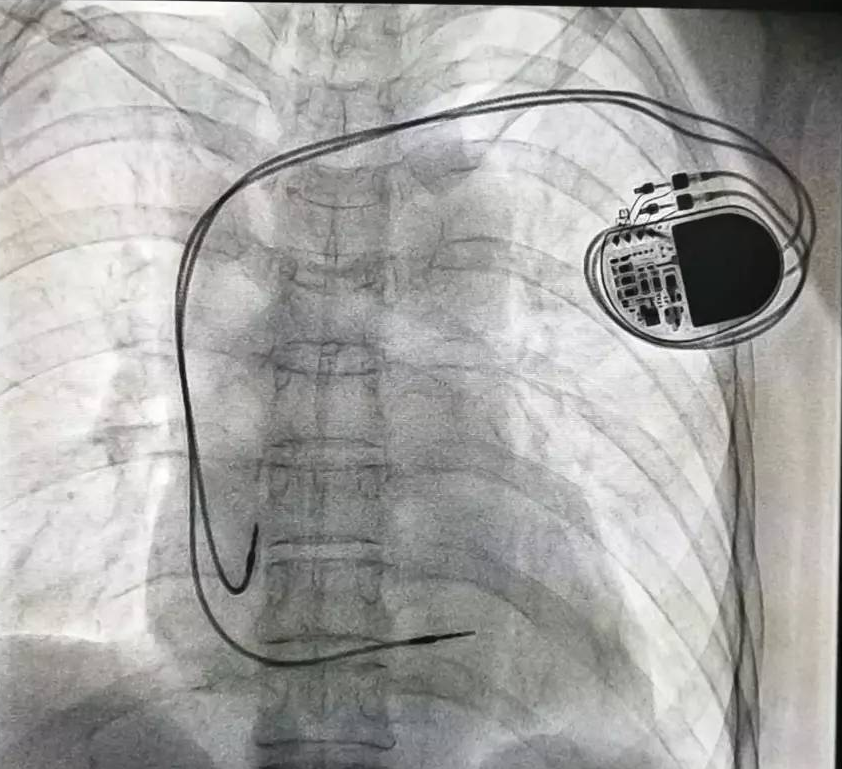

全球唯一!無線雙腔起搏器首次植入

來源:器械之家,未經(jīng)授權(quán)不得以任何形式轉(zhuǎn)載,且24小時(shí)后方可轉(zhuǎn)載。2022年2月7日雅培宣布,其在研型Aveir?雙腔無引線起搏器完成了全球首例患者植入,這也是全世界第一個(gè)雙腔無線起搏器。Aveir?DR雙腔起搏器提供右心房和心臟右心室的同步、逐次跳起搏,近80%接受起搏器治療的患者需要雙腔選擇,A